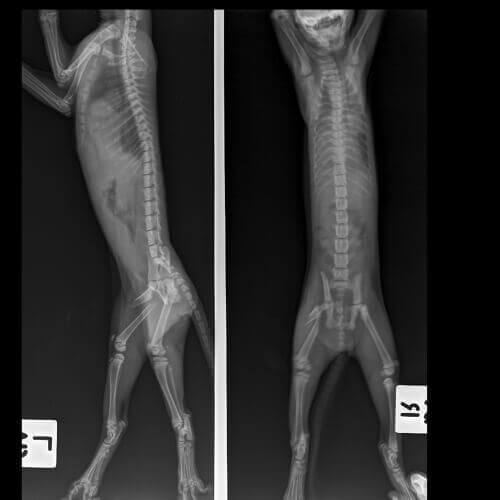

- RTG

Wiek Twojego kota, historia urazów, czy problem jest ostry czy przewlekły, stopień kulawizny oraz liczba dotkniętych nią łap to czynniki, które mogą pomóc wskazać źródło problemu.

Istotne jest, aby podkreślić, jak ważne jest postawienie właściwej diagnozy, aby Twój kot nie cierpiał na trwałe zaburzenia mięśniowe lub nerwowe. Twój weterynarz przeprowadzi pełne badanie kota, aby spróbować określić dokładną przyczynę problemu.